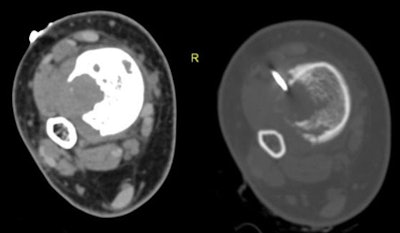

Egyptian researchers found that CT-guided percutaneous needle biopsy (PCNB) is accurate and effective for diagnosing lesions of the appendicular long bones -- offering a much-needed solution to the problem of indeterminate x-rays, according to an article in the European Journal of Radiology.

In all, 49 patients including 23 men and 15 women (mean age 33.7 years, range 4-77 years) underwent image-guided biopsies. Imaging in the cohort included radiography, CT, and MRI, and the study team categorized the records according to the location of the host bone, presence or absence of an extraosseous soft-tissue component (usually at MRI), and imaging nature of the lesion matrix (usually at CT) including lytic, sclerotic, or mixed lytic and sclerotic.

After bleeding, the researchers collected procedure parameters and lab markers. An experienced musculoskeletal radiologist performed all biopsies under CT guidance, with most patients in a state of conscious sedation so they could lie down comfortably, the authors wrote.

Cross-sectional imaging showed an extraosseous component in about half (26/49) patients, which facilitated biopsy and obviated the need for cortical breach, the authors wrote. The other 23 patients had completely intraosseous lesions that required more aggressive efforts to reach the lesion, the study team wrote.

Based on imaging findings at CT and x-ray, initial diagnostic yield was higher for mixed lesions (94%), followed by sclerotic (89%) and lytic (83%) lesions, according to the authors. As for the completely intraosseous lesions, the diagnostic yield was 74%, while the presence of extraosseous soft-tissue components raised the diagnostic yield to 100% in 26 cases.

"The image-guided percutaneous biopsy has proved to be a safe, minimally invasive, and cost-effective procedure for the diagnosis of skeletal lesions, obviating the need for the more risky and invasive open surgical biopsy in most patients, wrote Nouh and Abu Shady. "Meticulous technique regarding compartmental barriers, neurovascular structures, and seeding of malignant cells along the biopsy needle track are prerequisites for optimized treatment strategies with limb-salvage procedures. CT has proven to be a recognized modality for guiding PCNB of deep-seated musculoskeletal lesions."